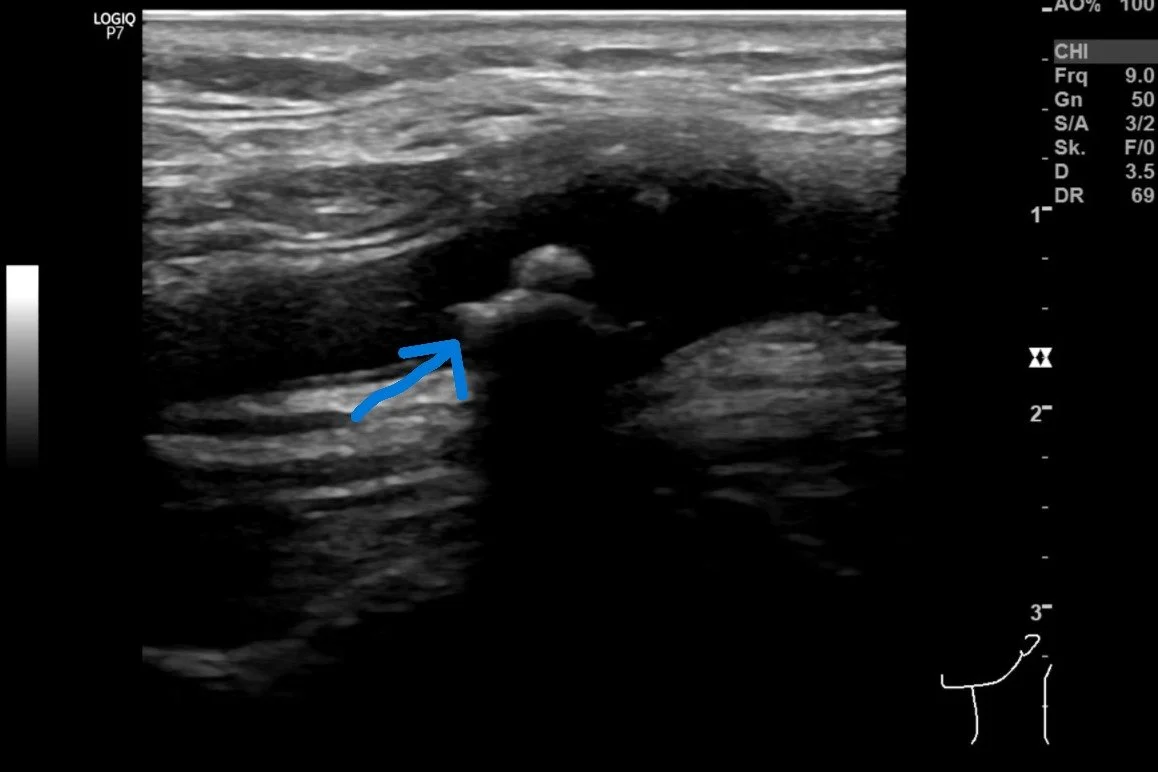

Frühzeitig erkennen, ob Gefäße verkalkt sind – der Ultraschall der Halsschlagader zeigt Ablagerungen, noch bevor Beschwerden entstehen. Warum Entkalker dabei keine Hilfe sind, lesen Sie im neuen Blogbeitrag.